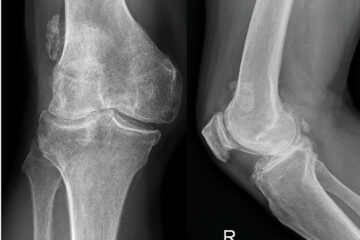

โItโs bone on boneโฆcaused by wear and tearโ, This is the common understanding of knee osteoarthritis (OA) affecting 9% of Australians. However, common misconceptions about knee OA negatively influence cliniciansโ referral to, and patientsโ acceptance of, nonsurgical management. Australian GPs are three times more likely to refer patients with knee OA for surgical opinion, than nonsurgical management. Read More...